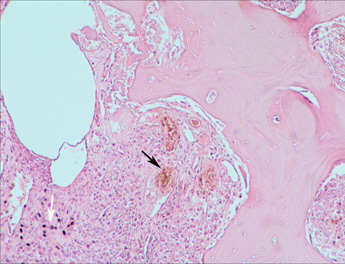

经组织学检查显示:镜下大量成骨细胞聚集,网状,细胞核细长,核质比高,深染细胞大量分布,非典型有丝分裂相较常见,部分区域有明显的成软骨细胞分布,骨质呈片状分布,组织间大量毛细血管网状分布,有出血,炎性细胞浸润(见图6-7)。淋巴结内大量圆形瘤细胞浸润,肿瘤已经淋巴结转移(见图8)。

图 6  大量成骨细胞聚集,细胞大小不一,核质比高,有毛细血管分布,

出血(黑色箭头所指),炎性细胞浸润(白色箭头所指)。(H.E.×100)

图 7  骨肉瘤。细胞核细长,非典型有丝分裂相常见。(H.E.×400)

图 8  骨肉瘤淋巴结转移。淋巴结内有大量圆形瘤细胞浸润(箭头所指)。(H.E.×400)